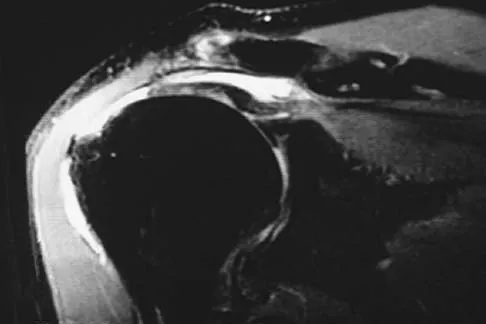

A 47-year-old man has acute right shoulder pain after falling off a ladder. The MRI scan shown in Figure 9 reveals

Explanation